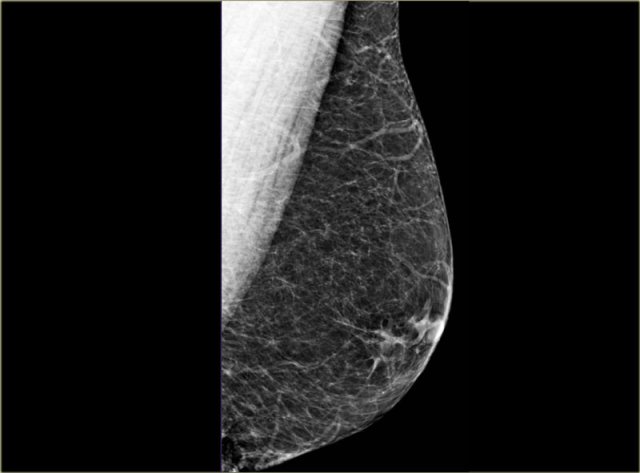

Normal male mammogram Normal male mammogram

On the left another normal male breast.

There is more fatty tissue and there are a number of blood vessels.

There is a small amount of fibrous connective tissue, but basically most of this breast is just fat.